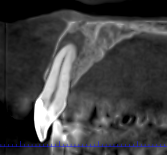

Las extracciones complejas, especialmente de terceros molares inferiores, suponen un reto quirúrgico cuando existe cercanía entre las raíces dentarias y

El CBCT (Tomografía Computarizada de Haz Cónico) es una de las herramientas diagnósticas más importantes en la odontología actual. Su

Los dientes incluidos, como caninos o muelas del juicio, son una situación frecuente en odontología. Aunque la ortopantomografía suele ser